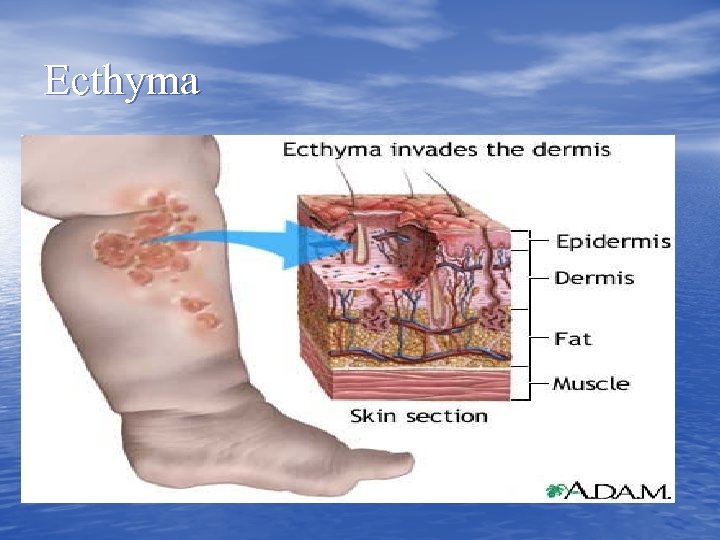

Skin & Soft tissue Infections Epidermis/Dermis • Impetigo • Folliculitis • Erysipelas • Ecthyma • Furuncle • Carbuncles

Skin & Soft tissue Infections Epidermis/Dermis • Impetigo • Folliculitis • Erysipelas • Ecthyma • Furuncle • Carbuncles

Ecthyma

Ecthyma

Ecthyma http: //www. lib. uiowa. edu

Ecthyma http: //www. lib. uiowa. edu